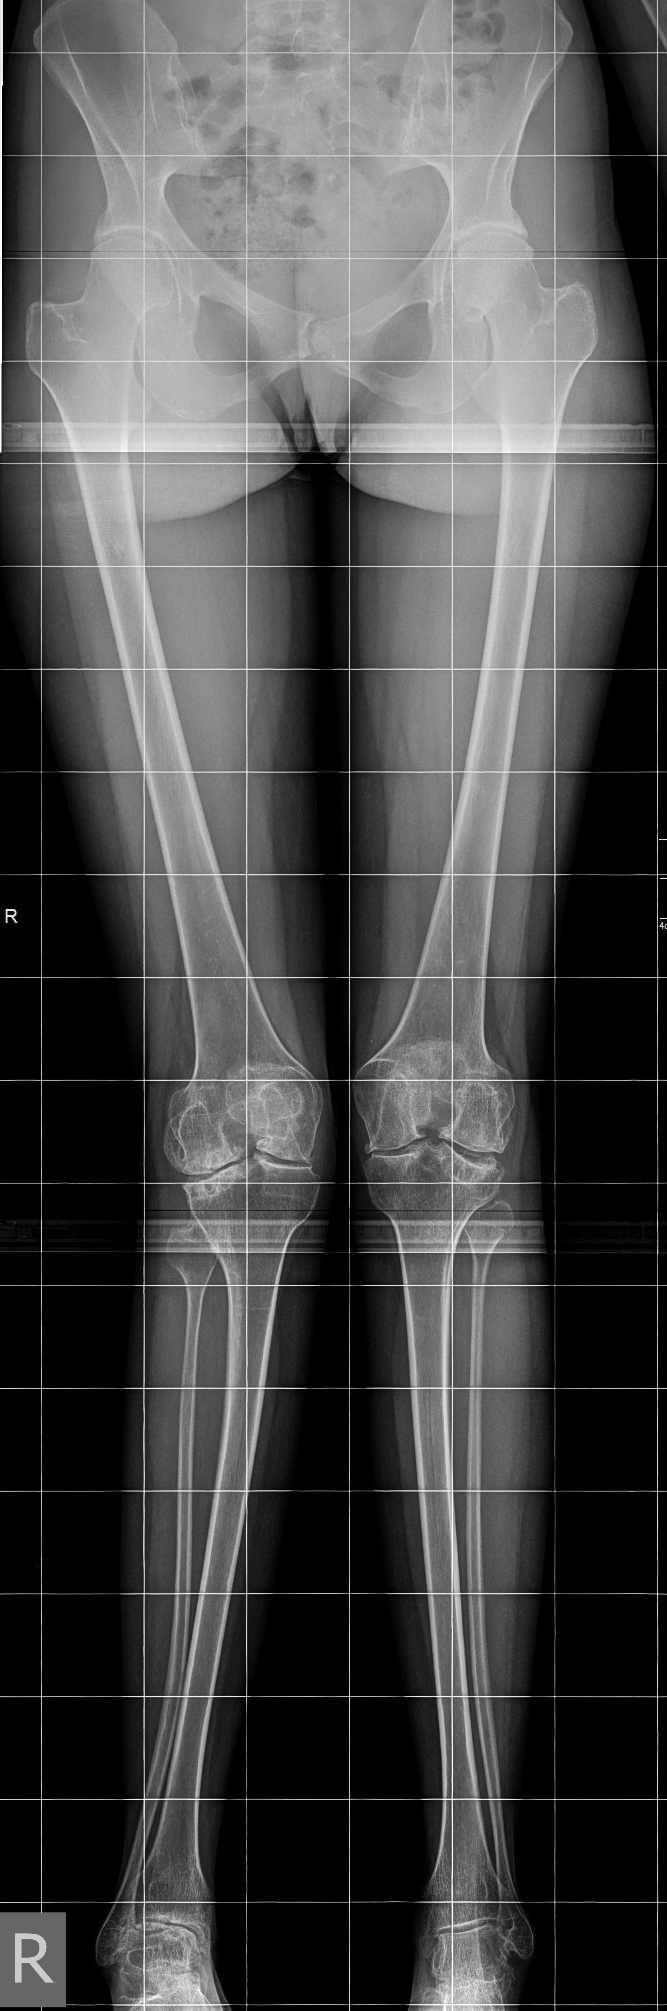

девушка 29 лет с ревматоидным артритом, социальная, лечение получает. вальгусную деформацию на уровне коленных суставов замечает около 10 лет, прогрессирует. Движения в правом коленном суставе:разгибание полное, сгибание около 95-100 град. Боли особой нет. Консультировалась в нескольких НИИ, рекомендовали эндопротезирование.У меня есть желание (вполне, возможно, что и глупое) за сустав "побороться", учитывая возраст, да и первичное протезирование будет не слишком простым. Может исправить деформацию, а там куда кривая судьбы заведет? больше беспокоит боль в голеностопе. В связи с этим есть несколько вопросов: 1. имеет смысл с этим заморачиваться? 2. если да, то в каком объеме? 3. может имеет смысл сделать коррекцию ниже метафиза с одномоментной фиксацией "приличным"гвоздем? Схема прилагается 4. насколько стоит опасаться тракционной нейропатии, стоит сделать острое укорочение или тянуть аппаратом? 5 . еще ряд вопросов, которые я не учел PS книгa Dror Paley пока утеряна вместе с жестким диском, потому не судите строго за дилетанство и приветствуются ваши схемы. Всем большое спасибо за понимание.

Коленный сустав в итоге надо будет протезировать. За что Вы там собрались бороться? Заболевание воспалительное и захватывает весь сустав, а не только его латеральный отдел. Очевидна варусная установка стопы, что можно попробовать устранить клиновидной остеотомией таранной кости и, возможно, артродезом